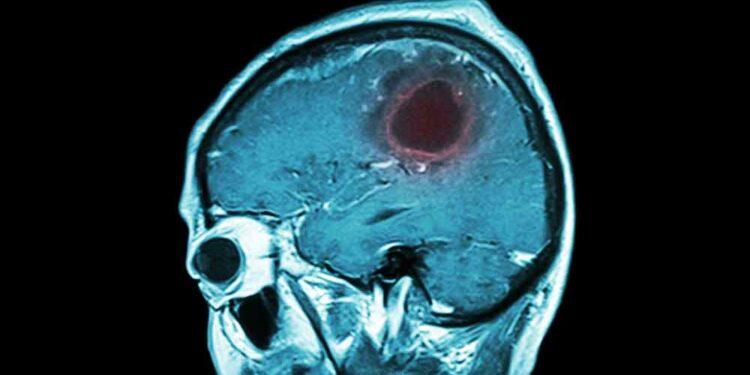

Operacioni u realizua pa prerje në kokë, pa shenja dhe pa dëmtuar nuhatjen tek një paciente 34-vjeçare, me një tumor 3 cm në tru, ngjitur me nervat e nuhatjes e të shikimit.